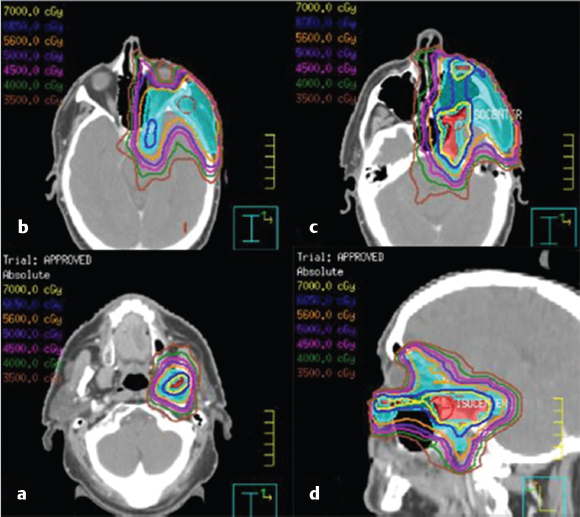

7 Role of Radiotherapy in the Treatment of Skin Malignancies Non-melanomatous skin cancers (NMSC), specifically basal cell carcinoma (BCC) and squamous cell carcinoma (SCC), are the most common malignancies in the United States. They are primarily managed surgically and carry an excellent prognosis, with a 1 to 5% rate of disease recurrence after complete excision and only exceedingly rare instances of distant metastasis. Historically, radiotherapy played a prominent role in the definitive management of these cancers as an alternative to surgical resection, especially in cosmetically sensitive areas. With the improvement in surgical techniques in recent decades, especially the widespread use of Mohs micrographic surgery (MMS), the use of curative radiation for skin cancers has declined. However, radiation is still commonly used in the definitive setting for patients with NMSC who are poor surgical candidates or have larger lesions in cosmetically sensitive regions of the face, and in the postoperative setting for more advanced tumors that have high-risk pathologic features that are associated with excessive risks of locoregional recurrence after surgery alone. Radiotherapy plays a similar role in the postoperative management of cutaneous melanoma. Radiation also offers excellent palliation for noncurable patients. This chapter reviews common indications, dose and fractionation schedules, techniques, and oncologic and cosmetic outcomes for radiotherapy for NMSC and melanoma ( Both surgery and RT can offer excellent cure rates for the management of early-stage NMSC. Surgery is typically the preferred method of treatment, given it can be performed in a single session, and has been associated with superior oncologic and cosmetic outcomes. One prospective randomized study compared the outcomes of MMS and definitive RT in 347 patients with less than 4 cm BCC of the face. The local failure rate was 0.7% for patients treated with MMS and 7.5% for patients treated with RT. Additionally, the cosmetic outcome was rated “good” or better more often in those patients who underwent surgery (87 vs. 69%).1 Though the technique of RT was not controlled (55% received interstitial brachytherapy and 45% received orthovoltage therapy), which could have affected the quality of the comparison, as the only randomized study, this trial remains pivotal in guiding medical decision making. A variety of factors can influence the decision to favor RT rather than surgery for NMSC. Typical contraindications to definitive RT include very large tumors and those with bone and/or cartilage invasion, given that control rates are typically inferior, as well as recurrent tumors that have been previously radiated or arise in an area of previous radiotherapy. Radiation should also be avoided in patients with genetic radiosensitivity syndromes, such as xeroderma pigmentosum and basal cell nevus syndrome, and in those with active connective tissue diseases, such as scleroderma and systemic lupus erythematosus.2 Patients who are candidates for definitive RT include those with unresectable disease, older patients with comorbidities limiting their surgical options, and patients with lesions involving the eyelid, canthi of the eye (especially those who carry surgical risk to the lacrimal duct), external ear ( Fig. 7.1 A modern linear accelerator, capable of delivering photon and electron radiotherapy with image guidance provided by cone beam CT (red arrow). A robust literature, much of it older when RT was more commonly used, supports the safety and efficacy of definitive RT for many of these aforementioned types of patients. A review of 986 BCC and SCC of the skin overlying the eyelid treated with definitive RT demonstrated a 5-year cure rate of 96.4%.3 A review of 334 BCC and SCC of the external ear at the Princess Margaret Hospital treated with definitive RT demonstrated a 2-year local control rate of 87%, with severe late toxicity noted in only 7% of patients.4 A review of 100 patients with SCC of the nasal skin at the Princess Margaret Hospital treated with definitive RT demonstrated a 2-year local control rate of 90%, with no severe toxicities observed.5 Fig. 7.2 (a) SCC of the helix of the left ear with bleeding (baseline). (b) After treatment with definitive radiation therapy (50 Gy in 20 fractions with electrons). There was complete remission with excellent cosmesis. Fig. 7.3 (a) A 96-year-old patient with right retroauricular BCC, T2N0M0 (baseline). (b) One month after treatment with definitive radiation therapy (50 Gy in 20 fractions with electrons). While definitive RT monotherapy can provide effective tumor control for T1–3N0 NMSC, T4 tumors and those with nodal metastases demonstrate inferior outcomes. Initial surgical management is recommended in these patients, often followed by adjuvant radiotherapy. T4 disease is defined as tumor invasion into the axial or appendicular skeleton or perineural invasion (PNI) of the skull base. The University of Florida reported a local control rate of just 53% at 5 years in patients with T4 BCC and SCC.6,7 In a review of 68 T4 BCC and SCC of the skin of the head and neck treated with definitive RT, local control rates were lower in patients with recurrent disease, compared to primary lesions (41 vs. 67%; p = 0.07) and the three most important prognostic indicators for inferior local control and cause-specific survival rates were bone involvement (p < 0.01), recurrent lesions (p < 0.01), and nerve involvement (p < 0.02).6 Even the more favorable lesions had local control rates of less than 70%. Similarly, a large retrospective review which included 531 BCC and SCC treated with definitive RT demonstrated local control rates of 94 and 89% for primary BCC and SCC tumors, respectively, and 86 and 68% for BCC and SCC recurrent tumors, respectively.8 In patients with nodal metastases, locoregional recurrence rates with definitive RT alone range from 30 to 50% and cancer-related mortality is as high as 30%.9 Such suboptimal outcomes support the use of intensification of treatment and multimodal therapy for these patients with advanced disease. In patients who are not eligible for initial surgical resection, concurrent cisplatin-based chemotherapy can be considered to enhance the effectiveness of radiotherapy. While there is no high-quality evidence demonstrating clear benefit to such an approach in cutaneous malignancies, many head and neck oncologists extrapolate from the mucosal SCC of the head and neck, where concurrent chemotherapy significantly improves disease control and survival in the setting of locally advanced disease treated nonoperatively.10 Fig. 7.5 A patient with multifocal BCC 3 months after treatment with definitive radiation therapy (40 Gy in 10 fractions with electrons). Postoperative RT is rarely used for BCC. Patients with BCC have an exceedingly low risk of recurrence after surgery alone, and even patients with a positive margin, focal cartilage invasion, or PNI are often still candidates for close observation and salvage re-resection if needed.11,12 However, postoperative RT is often considered in cases where there are persistently positive margins after multiple resections, T4 disease that extensively invades bone or soft tissue, lymph node metastasis, or clinically apparent PNI ( Postoperative RT is much more commonly used in resected SCC ( Retrospective data have demonstrated high rates of local recurrence in patients with T4 tumors managed with surgery alone.7 In addition, the rate of occult lymph node metastasis is high, ranging from 29 to 50%, in patients with advanced T-stage disease. In patients with deeply infiltrative (≥ 8 mm) tumors, or tumors that extensively invade deep subcutaneous fat, occult lymph node metastasis can be as high as 30%.9 Patients with recurrent primary tumors, PNI, lymphovascular space invasion, and those that are immunosuppressed are at significantly higher risk for having lymph node metastases and should undergo careful evaluation for regional disease with a contrast-enhanced diagnostic neck computed tomography (CT) and/or a positron emission tomography scan.14,15,16 In these patients, sentinel lymph node biopsy and/or neck dissection is recommended in conjunction with resection of the primary tumor. Postoperative RT can also be useful as an elective treatment to the undissected neck. Fig. 7.6 (a) A patient with right brow/forehead SCC (baseline). (b) One month after definitive radiation therapy (45 Gy in 15 fractions with electrons). Fig. 7.7 (a) An 88-year-old man with left temporal SCC in situ (baseline). (b) One month after treatment with definitive radiation therapy (30 Gy in five fractions with electrons). For patients with clinically involved lymph nodes, a therapeutic neck dissection followed by postoperative RT is the current standard of care. Although lymph node metastases are rare in SCC of the skin overall (~ 5%), they are clearly associated with a poor prognosis. After neck dissection alone, locoregional recurrence rates are 11 to 38% and even after multimodality therapy, the 5-year disease-free survival rates are 60 to 70%. Independent predictors of worse survival in this population include increased nodal size ≥ 3 cm, multiple lymph node involvement, extracapsular extension, incompletely excised nodes, and surgery monotherapy.15,16,17 A review of 167 patients in Australia with SCC metastatic to the parotid or cervical nodes compared outcomes for surgery versus combination of surgery and postoperative RT at a median dose of 60 Gy in 30 fractions. The use of postoperative RT was associated with significantly lower rates of locoregional recurrence (20 vs. 43%), and higher 5-year disease free (73 vs. 54%; p = 0.004), and 5-year overall survival (66 vs. 27%; p = 0.003) compared to patients who received surgery alone.16 Similar results supporting the benefit of postoperative RT for locoregional control and 5-year disease-free survival in patients with cutaneous SCC metastatic to lymph nodes and/or periparotid lymph nodes have been reproduced in a number of retrospective reviews.18,19,20,21 For patients who received lymph node dissection for primary SCC located on the trunk or extremities, postoperative RT is typically recommended when multiple nodes are involved or extracapsular extension is present. Similar to mucosal SCC of the head and neck, RT can be avoided in immunocompetent patients with a single involved lymph node, smaller than 3 cm, without extracapsular extension on parotidectomy or cervical lymph node dissection, as rate of regional recurrence is less than 5%.22 Fig. 7.9 A 91-year-old man with a history of extreme kyphosis and multiple facial SCC, who presented with a rapidly enlarging right neck mass, treated with surgical resection and free flap reconstruction. (a) Axial slice depicting isodose coverage of the neck bed with electron radiation therapy. (b) Extreme kyphosis dose coverage using 30 Gy in five fractions twice weekly. Fig. 7.10 A 63-year-old man with multiple recurrent SCC of the right temple with Mohs map overlying the site of the tumor. Fig. 7.11 (a) Coronal CT slice of dose distribution for postoperative radiation therapy after Mohs surgery for tumor depicted in PNI, while not common (5–10% of SCC), is another important risk factor for recurrence that should be weighed in the decision to administer adjuvant RT. PNI is typically divided into clinical and microscopic PNI. Clinical PNI is defined by neurologic manifestations, most commonly involving the trigeminal or facial nerves, leading to pain, paresthesias, paralysis, formication (the sensation of bugs crawling on the skin), or radiographic evidence of nerve enhancement.23,24 Microscopic PNI is appreciated only histologically and is identified after surgery in a patient who was asymptomatic preoperatively. PNI is important given it is associated with increased risks of local recurrence as well as regional and distant metastases. Factors associated with increased risk for SCC with PNI include male sex, tumor size greater than 2 cm, midfacial tumor location, recurrent tumor, and poorly differentiated subtypes.25 The degree of PNI is predictive of risk of recurrence; therefore, a careful history as well as physical and imaging examination is critical. Magnetic resonance imaging (MRI) has the advantage of identifying the extent of macroscopic disease through nerve enlargement or enhancement or obliteration of the normal fat plane surrounding a nerve ( The difference between clinical and microscopic PNI was highlighted in a series from the University of Florida which compared the outcomes of patients with PNI treated aggressively with surgery and postoperative RT. Those with clinical PNI had significantly lower 5-year rates of local control (57 vs. 90%; p = < 0.001) and overall survival (57 vs. 69%; p = 0.03) compared to those found to have microscopic PNI.13,23 RT is therefore always recommended in cases of clinical PNI. The role of postoperative RT in patients with pathologic PNI is less clear. Lin et al found that focal versus extensive microscopic PNI carries different prognoses, with relapse-free survival better in the former group (86 vs. 74%; p =0.1).24 Unfortunately, the distinction between focal and extensive was not well defined. As such, adjuvant RT is not recommended in immunocompetent patients with nonrecurrent disease, in whom one or two isolated areas of PNI are found in small unnamed nerves, with a diameter of less than 0.1 mm, given the outcome is expected to be fairly good with surgery alone. However, patients with microscopic PNI, that is multifocal, involves larger nerves (> 0.1 mm in diameter) and named nerves, or occurs in immunosuppressed patients, are at higher risk and thus adjuvant RT is recommended.2,25 For irradiation of clinical PNI, the clinical target volume should include areas at high risk of failure, specifically the involved nerve, the portion of the nerve proximally at the skull base, the distal skin innervated by the nerve, major communicating branches, and the compartment in which the nerve is embedded.26 For example, for patients with CN VII involvement, the area of treatment should be tracked back to the nerve’s exit through the stylomastoid foramen, with care taken to administer adequate coverage of the geniculate ganglion by avoiding excessive restriction of the radiation dose delivered to the ipsilateral cochlea. Similarly, with V1/V2 nerve involvement, the gasserian ganglion in Meckel cave and the cavernous sinus should be targeted ( Another consideration highly relevant to radiation field design is the observation that PNI may also be associated with increased nodal failure in addition to recurrence in the tumor bed and along the nerve pathway. Lin et al demonstrated that patients who developed recurrent disease with pathologic PNI had a significantly higher risk of local recurrence (40 vs. 19%; p < 0.01) as well as regional recurrence (29 vs. 5%; p = 0.02).24 It is important to consider the location of the lesion in such scenarios, given that tumors on the scalp, for example, may be less likely to metastasize to lymph nodes, compared to cheek, ear, or nasal skin lesions. Understanding the drainage patterns of these tumors is crucial (e.g., parotid nodes for head and neck sites, axilla for trunk and extremity lesions) and should be incorporated into radiation targeting. Fig. 7.13 (a) Axial radiation planning CT slice depicting inferior alveolar nerve (solid red) covered by isodose lines. (b) Axial radiation planning CT slice depicting left cavernous sinus and temporal musculature (solid light blue) covered by isodose lines. (c) Axial radiation planning CT slice depicting course of V2 into cavernous sinus (solid red) covered by isodose lines. (d) Sagittal radiation planning CT slice depicting coverage of V1 and V2 back to the cavernous sinus (solid red) covered by isodose lines. Fig. 7.14 (a) A 67-year-old man with history of recurrent right auricular SCC treated with multiple surgical resections and prior irradiation who presented with recurrent disease at the right skull base (red arrow). (b) Sagittal radiation planning CT slice depicting recurrent disease covered by 70 Gy isodose line (black line). Melanoma is believed to be a relatively radioresistant malignancy. Therefore, maximal surgical resection is paramount in the management of these tumors. RT has limited benefit in achieving long-term control in the presence of gross disease. RT is delivered to gross melanoma in patients deemed to have unresectable disease, or those with rapid postoperative recurrence who have failed surgical management. In these cases, higher doses per fraction are generally preferable and the intent of treatment is largely palliative. Adjuvant radiotherapy to the primary tumor bed, nodal basin, or both, has been studied as a means of reducing locoregional recurrence. If adequate margins are obtained, local recurrence for primary melanoma is infrequent, with rates consistently reported to be less than 5%.27,28 However, there is a smaller subset of patients with higher rates of failure in the tumor bed, including deeply invasive T4 disease, the presence of satellitosis, the presence of desmoplastic subtype, or persistently positive margins despite multiple attempts at excision. In these cases, adjuvant RT to the primary tumor bed should be considered ( O’Brien and colleagues analyzed 629 patients with head and neck melanoma and found that increased local recurrence rates were associated with increased tumor thickness: < 0.76 mm, 2%; 0.76 to 1.49 mm, 5%; 1.5 to 3.99 mm, 15%; and ≥ 4 mm, 20%.29 Typically, adjuvant RT is considered for T4 tumors, although typically reserved for those with additional high-risk features. One of which is satellitosis, which represents discontiguous sites of disease within 2 cm of the primary tumor and is known to be a marker of increased recurrence risk.30 Desmoplastic melanoma is a rare histologic subtype (1% of all melanomas) and is characterized by spindle-shaped cells with associated collagen production. This subtype is often associated with perineural spread and local recurrence rates have been reported as high as 20 to 50%.31,32 In these cases, based on the relatively higher risk for local recurrence, adjuvant RT should be considered. More extensive literature guides the use of adjuvant RT to nodal basins, both in the elective setting and following lymph node dissection.33,34 Data supporting the benefit of RT in reducing regional recurrence come from the randomized phase III study by Burmeister et al in which higher risk patients were randomized to surgery and lymph node dissection with or without adjuvant radiation to the nodal basin.35 Eligible patients had one of the following features associated with increased failure rates: 1. Serum lactate dehydrogenase < 1.5 times the upper limit of normal and the presence of extracapsular extension (ECE). 2. ≥ 1 involved parotid node of any size. 3. ≥ 2 involved cervical nodes and/or ≥ 3 cm of tumor within a node. 4. ≥ 2 involved axillary nodes and/or ≥ 4 cm of tumor within a node. 5. ≥ 3 involved inguinal nodes and/or ≥ 4 cm of tumor within a node, and/or recurrent disease.27,30 Importantly, no systemic therapy was delivered in this trial. In the 217 patients included on the study, those who received RT were significantly less likely to experience regional recurrence compared to those in the observation arm (18 vs. 33%; p = 0.041). As distant metastasis is the predominant mode of melanoma disease failure, it was not surprising that an improved rate of regional control did not translate into an overall survival average (54 vs. 44%; p = 0.12). The most common Grade 3 or 4 adverse events were seroma and wound infections, which were equivalent in both arms.35 The lack of systemic therapy in this study as well as the lack of a survival difference with the use of RT has raised the question of the true benefit of adjuvant RT for all patients eligible for this study. That said, it reinforces the guiding principle where locoregional control is a priority, and in a case with extensive nodal disease, especially with extranodal extension and significant soft-tissue involvement, adjuvant RT should be considered as a proven way to reduce rates of locoregional recurrence ( Fig. 7.15 A 72-year-old man with pT3N2cMx melanoma of the scalp with ulceration and satellitosis treated with wide local excision, free flap reconstruction, ipsilateral neck dissection, and adjuvant RT to the primary tumor bed. (a) Postoperative image. (b) Axial radiation planning CT slice demonstrating bolus material (red arrow) for achieving adequate surface dose.

Fig. 7.13). Targeting the nerve root as it exits the brainstem should be considered for nerves that are radiographically involved at the skull base. For patients with unresectable disease invading the skull base, high-dose radiation (70 Gy), with or without concurrent chemotherapy, is required (

Fig. 7.14).